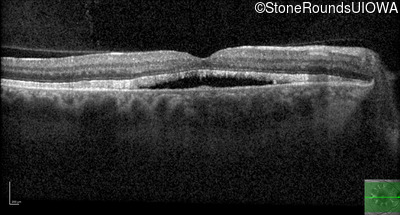

Age at visit: 49 years

This 49 year old man first experienced some mild metamorphopsia at age 35.

Age at visit: 51 years

Age at visit: 52 years